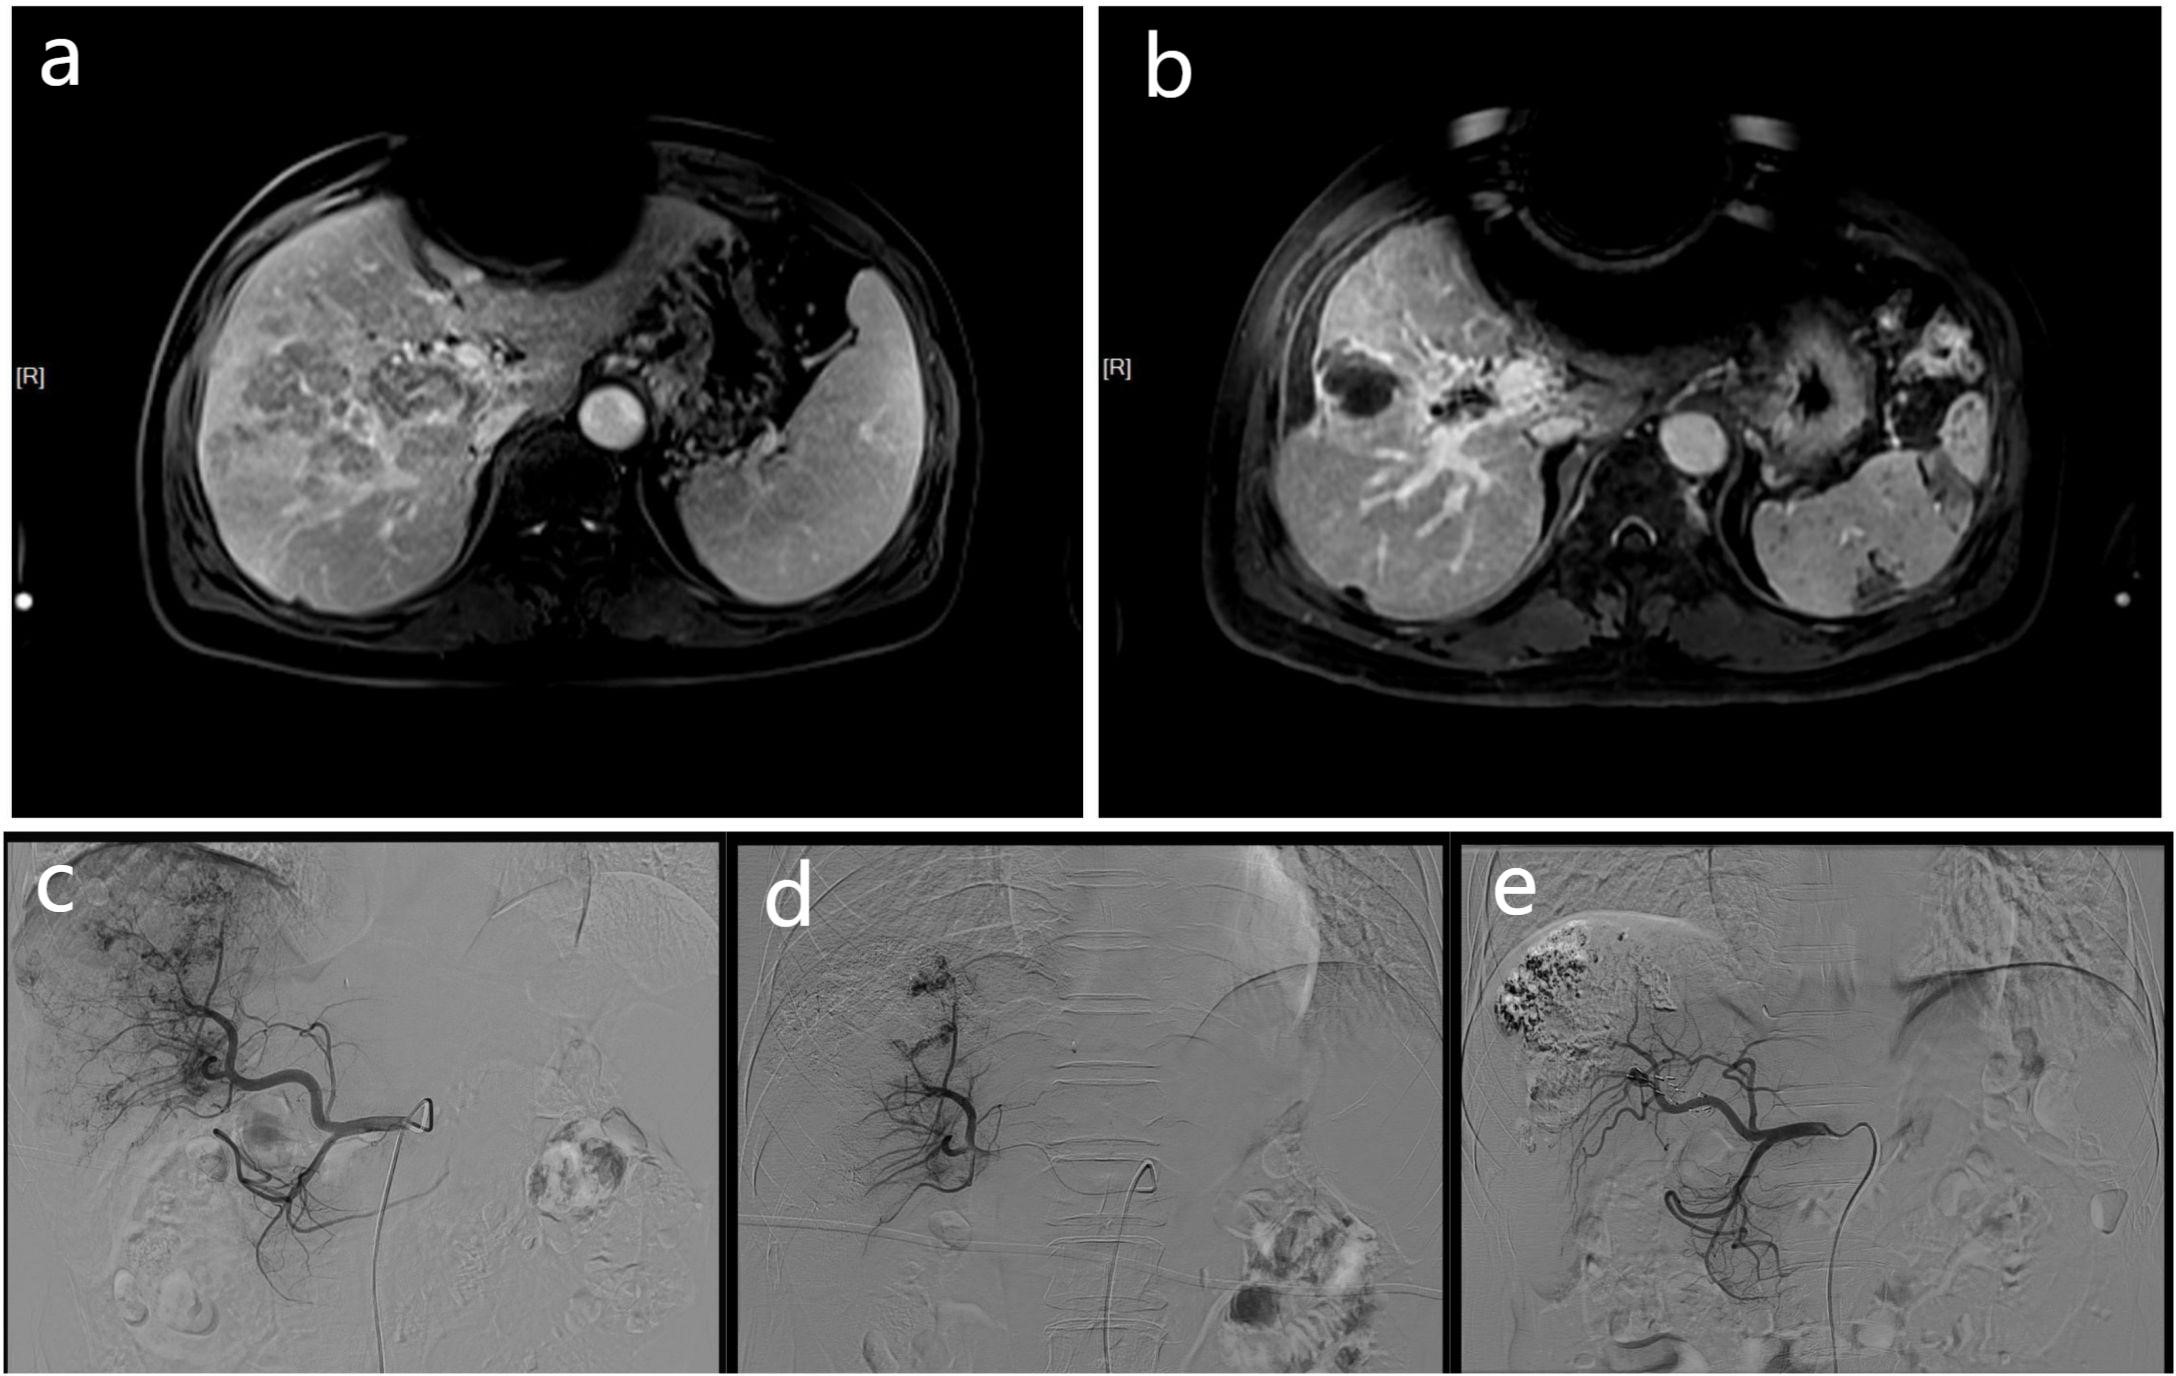

Figure 1 These MR and DSA images show the imaging data of a 68-year-old men with HCC complicated by portal vein tumor thrombosis in the right branch. Contrast-enhanced MR scan showing a tumor thrombus in right portal vein (A). The contrast-enhanced MR of the patient 3 months later shows a significant reduction in PVTT volume (B), and the previously blocked portal vein due to PVTT also restores blood flow. At the same time, according to the mRECIST criteria, there was no activity in the intrahepatic lesions, and no activity was found in the PVTT, which was judged as CR. The DSA image of the patient undergoing embolization of the APFs and obvious portal vein development can be seen during angiography of the proper hepatic artery (C). The angiographic image of the patient taken at a time after treatment, showing that the APFs are completed by sealing (D). A follow-up DSA image of the patient three months later showed no APFs (E).